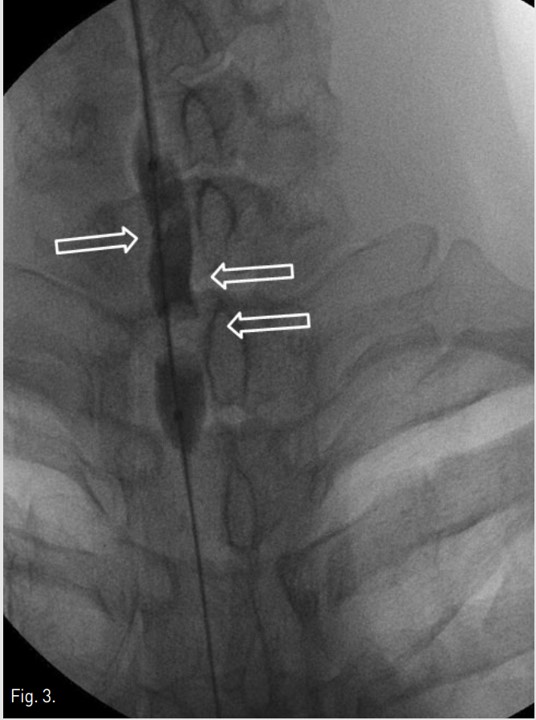

Fig. 3.

Fig. 3 Fluoroscopic image shows waist deformity of balloon at lower cervical trachea during balloon dilation.